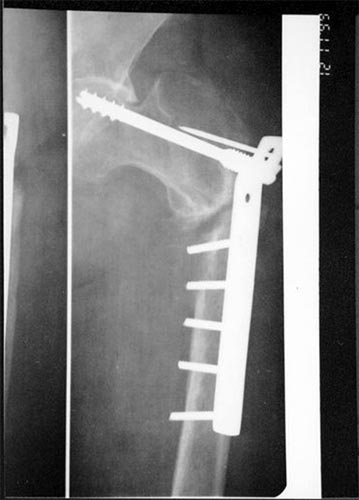

以上图片为三位患者的X线片,显示股骨粗隆下骨折、骨不连,内固定已经失败。

主要采用股骨重建髓内钉获得良好早期的稳定性,为骨愈合创造条件,